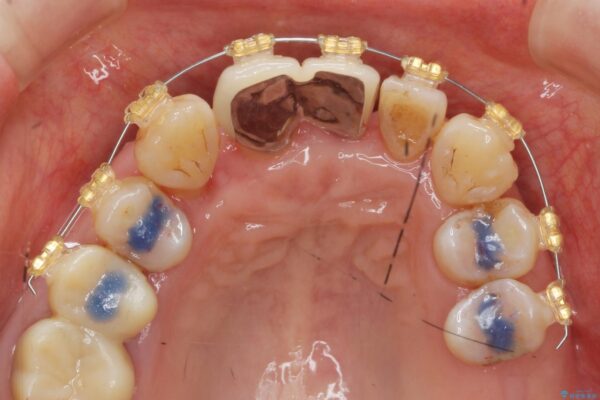

• 矯正装置:ワイヤー矯正

まず、保存の難しい歯を抜去したのち矯正治療を行い歯並びの改善、歯周ポケットを除去したことで安定した歯周環境、咬合関係を作り出すことができました。

矯正治療を事前に行ったことで全ての歯の神経を温存しセラミックブリッジを装着することができました。

治療中

歯の総合的なマネージメントを行う包括的歯科治療の実践[ 歯周病・矯正・セラミック補綴 ] 治療中画像 歯の総合的なマネージメントを行う包括的歯科治療の実践[ 歯周病・矯正・セラミック補綴 ] 治療中画像 歯の総合的なマネージメントを行う包括的歯科治療の実践[ 歯周病・矯正・セラミック補綴 ] 治療中画像 歯の総合的なマネージメントを行う包括的歯科治療の実践[ 歯周病・矯正・セラミック補綴 ] 治療中画像 歯の総合的なマネージメントを行う包括的歯科治療の実践[ 歯周病・矯正・セラミック補綴 ] 治療中画像 歯の総合的なマネージメントを行う包括的歯科治療の実践[ 歯周病・矯正・セラミック補綴 ] 治療中画像 歯の総合的なマネージメントを行う包括的歯科治療の実践[ 歯周病・矯正・セラミック補綴 ] 治療中画像 歯の総合的なマネージメントを行う包括的歯科治療の実践[ 歯周病・矯正・セラミック補綴 ] 治療中画像 歯の総合的なマネージメントを行う包括的歯科治療の実践[ 歯周病・矯正・セラミック補綴 ] 治療中画像 歯の総合的なマネージメントを行う包括的歯科治療の実践[ 歯周病・矯正・セラミック補綴 ] 治療中画像 歯の総合的なマネージメントを行う包括的歯科治療の実践[ 歯周病・矯正・セラミック補綴 ] 治療中画像